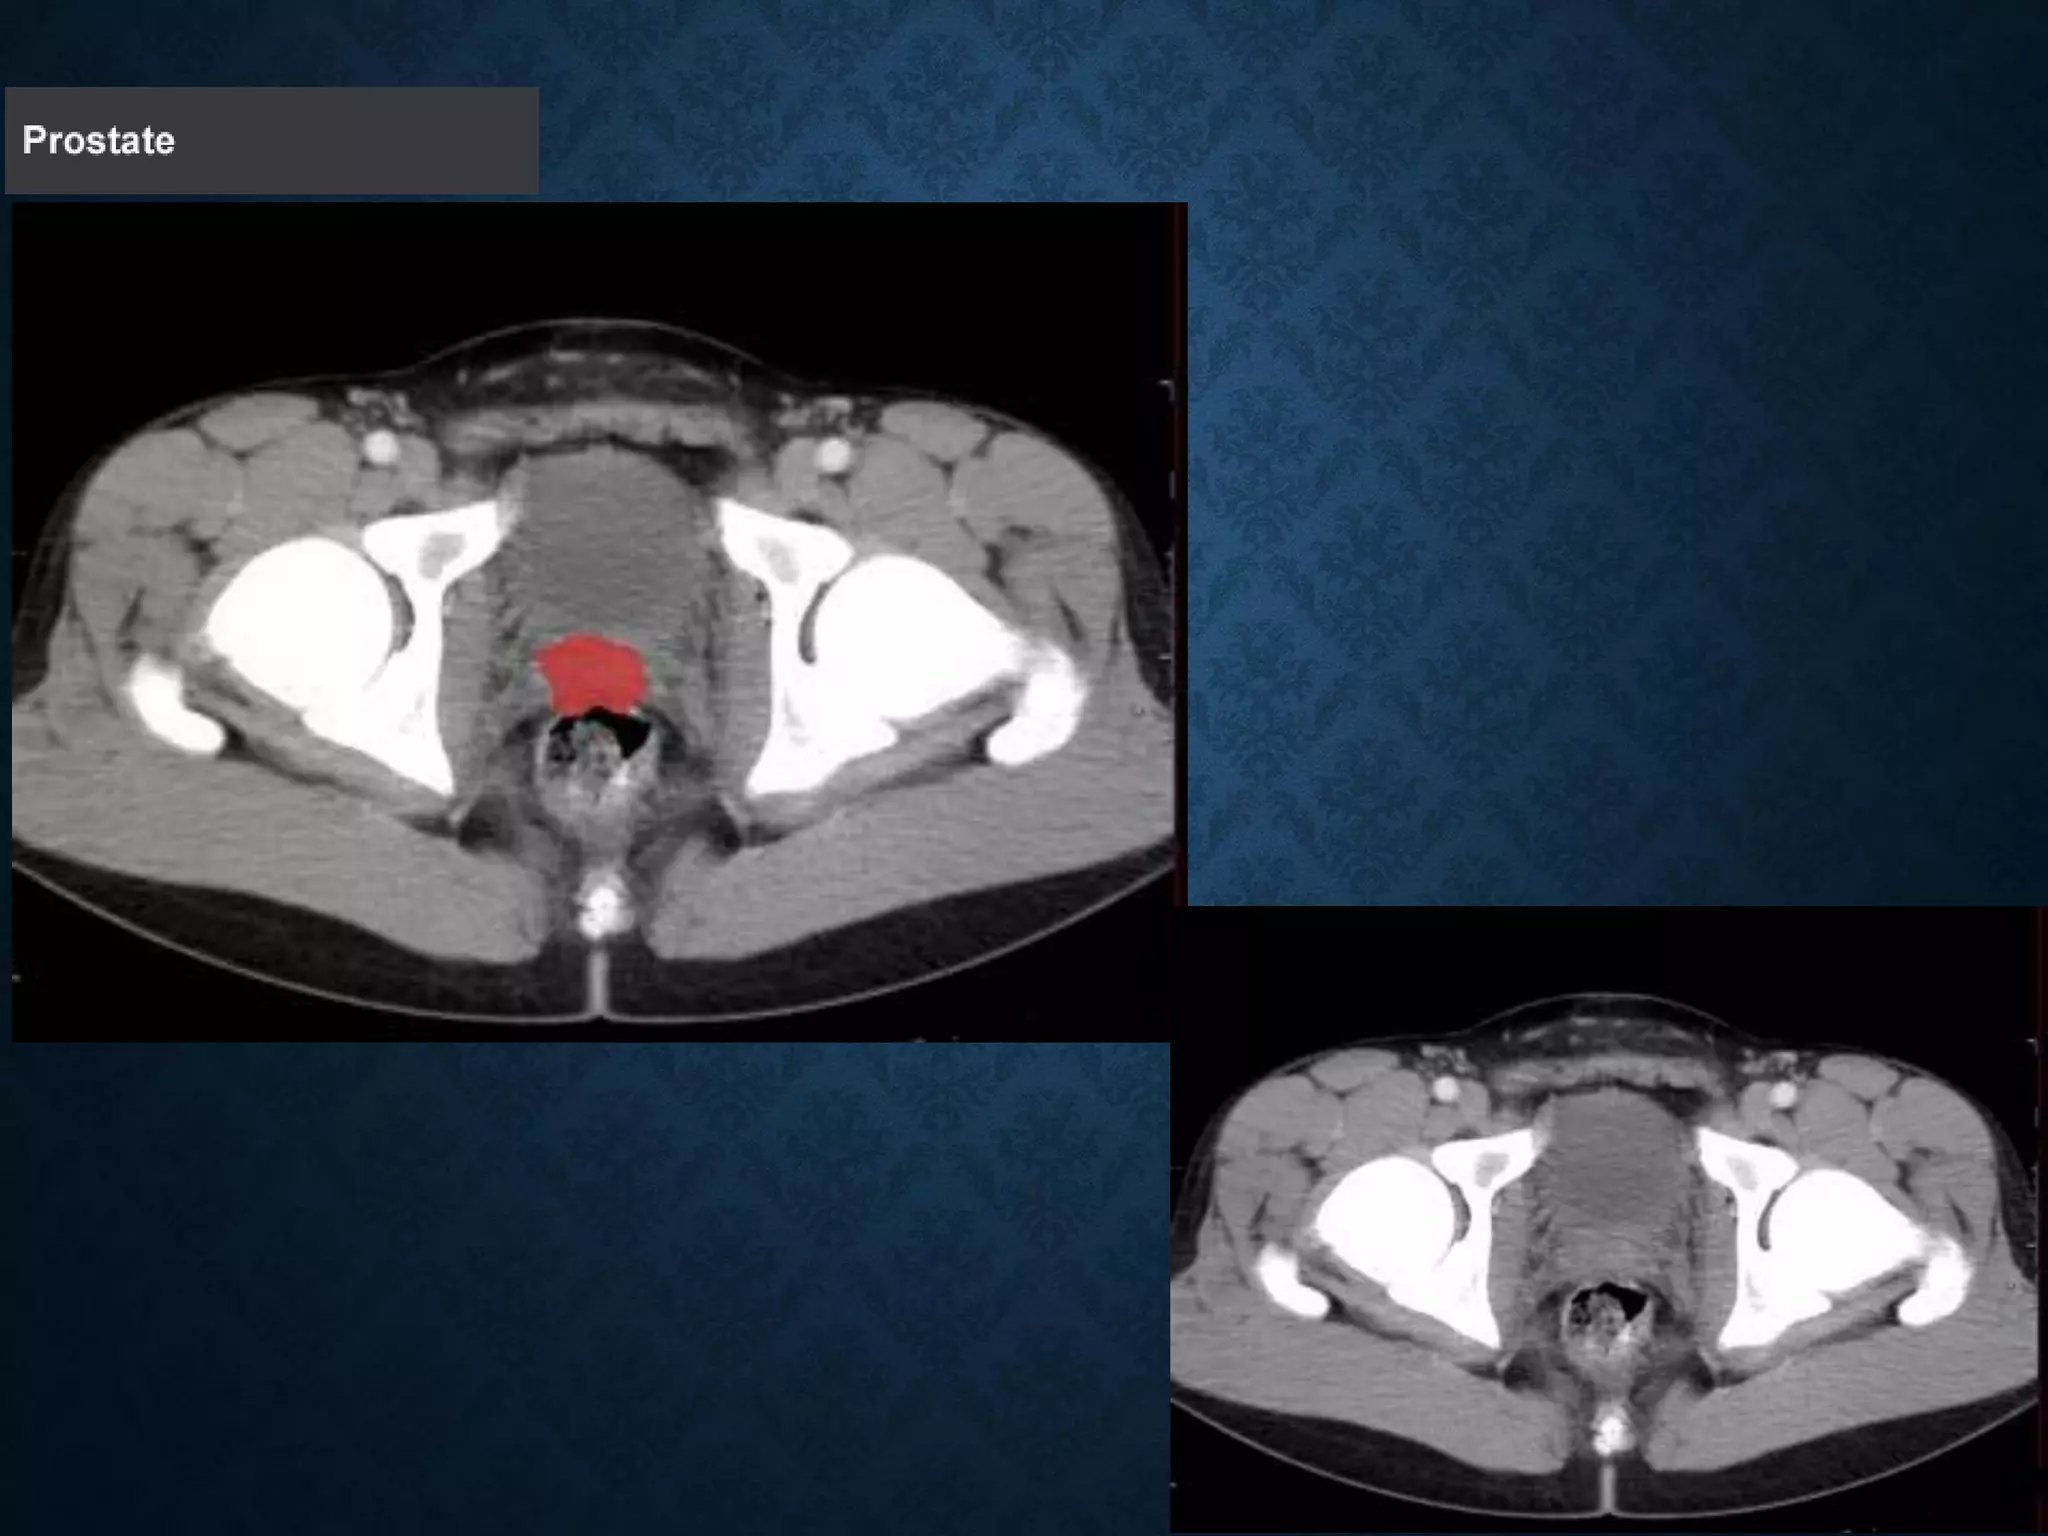

Identify the following structures in the body CT to the right. To view the location of the structure in the image click on

the label at the left and the structure will be indicated in the image. Abdominal CT scans typically begin just above

the diaphragm, so the first slice you see is of the lower chest.